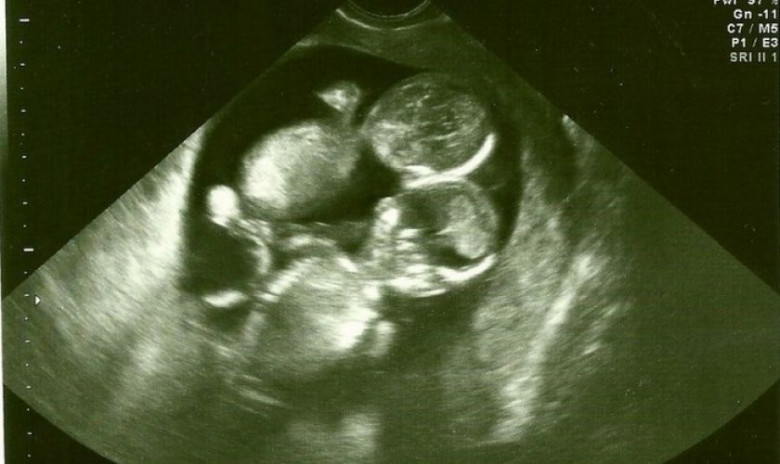

На 10-й неделе беременности, перенеся тяжелую простуду, женщина пришла на осмотр за несколько дней до запланированной даты. Там она и узнала, что ждет не одного, а сразу двоих малышей. Однако следующие слова медика ввергли Кейт в шок!

Дети, которые находились в утробе будущей матери, были моноамниотическими близнецами. Между этими крохами в животе нет перегородки, поэтому вероятность обвития пуповиной увеличивается в разы. Более того, на поздних стадиях беременности пуповины могут перепутаться друг с другом, повышая риск удушения для одного или обоих младенцев.

Кейт с мужем нашли лучших специалистов и следовали их рекомендациям. Сначала женщина ложилась на УЗИ раз в две недели. После 24-й недели беременности процедуры стали еженедельными.

После 28-й будущую мать положили в больницу, где врачи каждый день осматривали ее живот. А на 32-ю неделю беременности медики назначили кесарево сечение.